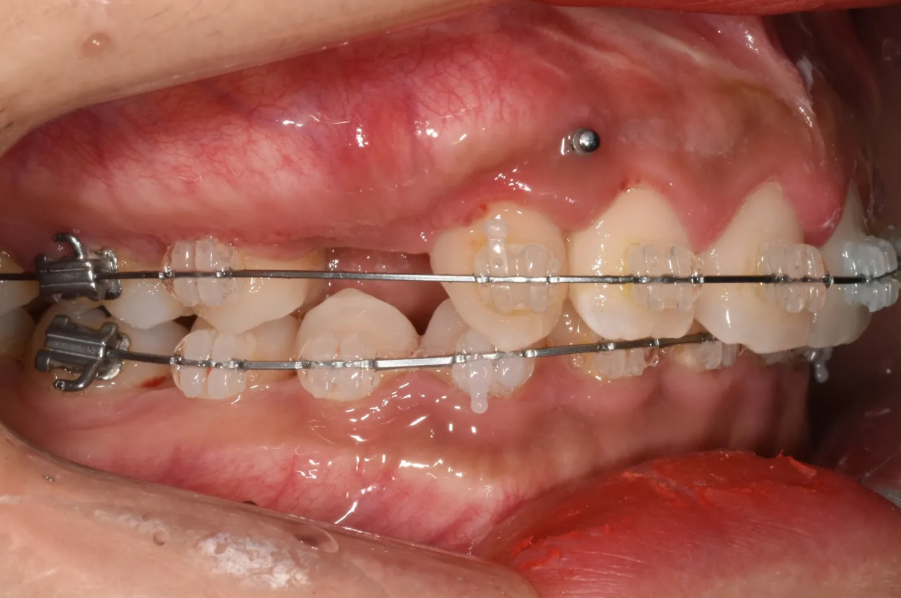

측면 모습. 발치한 공간으로 위쪽 앞니들을 당겨 넣게 됩니다.

위·아래 모두 교정 장치(브라켓)를 부착하고, 치열궁 확장과 과개교합 개선을 동시에 진행했습니다. 여러 가지 문제를 한꺼번에 효율적으로 해결하기 위한 전략이었습니다.